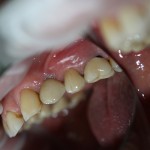

Через несколько месяцев, когда мы подойдем к финишу комплексного стоматологического лечения, мы поменяем эту коронку на постоянную, из керамики. И внешний вид, цвет и фактура будут совершенно другими. Как, например, в этом случае:

Попробуйте на этой фотографии найти коронку на импланте. Ответ — в апдейте через несколько дней.